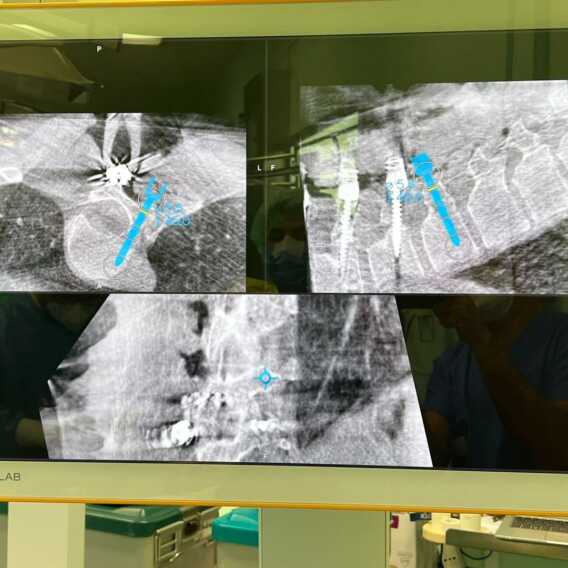

È stato effettuato al Policlinico di Bari il primo intervento computer assistito di correzione di scoliosi in Puglia. Attraverso il nuovo apparecchio acquistato dall’azienda ospedaliero-universitaria, dotato di navigatore e amplificatore di brillanza in 3D, è stato possibile aumentare l’accuratezza e la precisione dell’operazione chirurgica.

«La chirurgia computer assistita – ha spiegato Andrea Piazzolla, responsabile Chirurgia vertebrale della struttura – effettua una scansione navigata tridimensionale della colonna vertebrale che, integrando le immagini con tac e risonanza magnetica eseguite preventivamente, ricostruisce su due monitor una sorta di modellino: questo permette al chirurgo di pianificare pre-operatoriamente il posizionamento delle viti calcolando le “coordinate” da seguire».